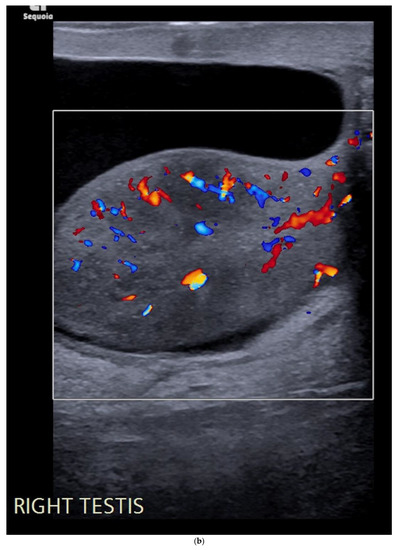

4.1. Seminomatous Germ Cell Tumour

| Seminomas | Homogenous and hypoechoic Well circumscribed Occasionally contain cystic components or calcifications |